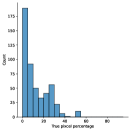

A few sample images and the corresponding masks of the polyp dataset in HyperKvasir are shown in Fig 2. The polyp images are RGB images. The masks of the polyp images are single-channel images with white () for true pixels, which represent polyp regions, and black () for false pixels, which represent clean colon or background regions. In this dataset, there are different sizes of polyps. The distribution of polyp sizes as a percentage of the full image size is presented in the histogram plot in Fig 3, and we can observe that there are more relatively small polyps compared to larger polyps. Additionally, a subset of this dataset was used to prove that the performance of segmentation models trained with small datasets can be improved using our SinGAN-Seg pipeline, and the whole dataset was used to show the effect of using SinGAN-Seg generated synthetic images instead of a large dataset which has enough data to train segmentation models. In this regard, this dataset was used for two purposes:

To understand the difference between the mask distribution of real images and synthetic images, we plotted pixel distribution of masks of synthetic images in Fig 6. This plot is comparable to the pixel distribution presented in Fig 3. The randomness of the generations made differences in the distribution of true pixel percentages compared to the true pixel distribution of real masks of real images. However, the overall shape of synthetic data mask distribution shows a more or less similar distribution pattern to the real true pixel percentage distribution.